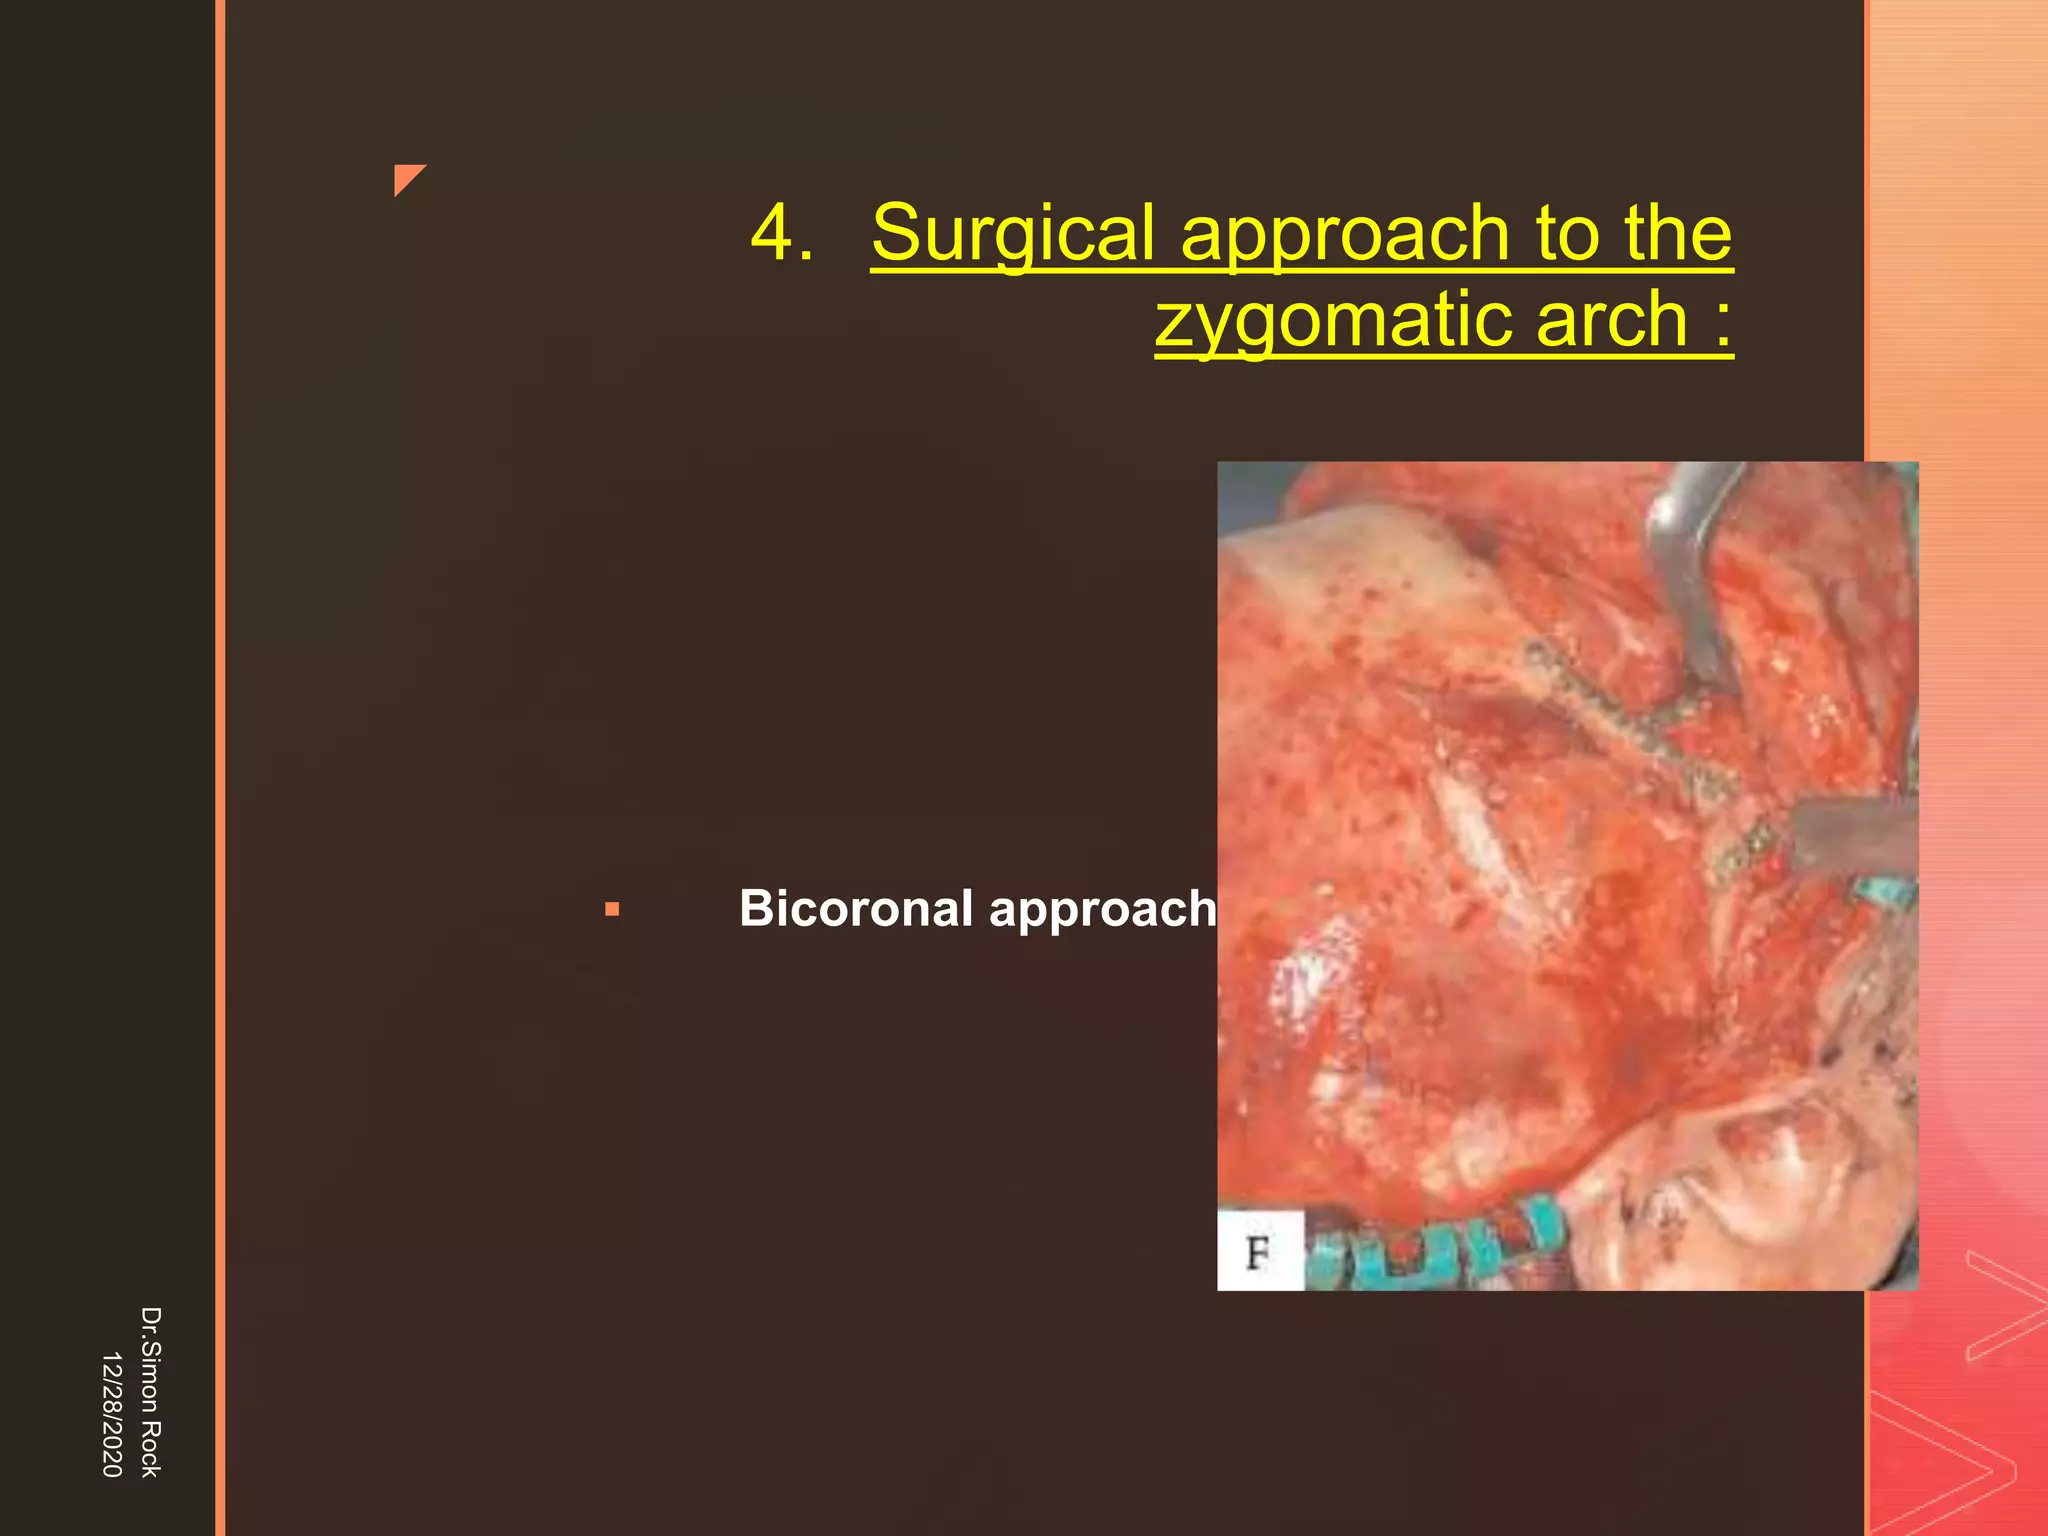

This document discusses the anatomy and fractures of the zygomatic bone. It notes that the zygoma forms the cheekbone and articulates with several other facial bones. Zygomatic fractures most commonly occur in the arch or body due to blunt trauma. Diagnosis involves checking for diplopia, ecchymosis, and other signs of orbital or facial bone involvement. Treatment may involve closed or open reduction based on the severity of displacement. Closed reduction techniques try to elevate the bone back into position without surgery, while open reduction requires surgical exposure and fixation of the fracture site.